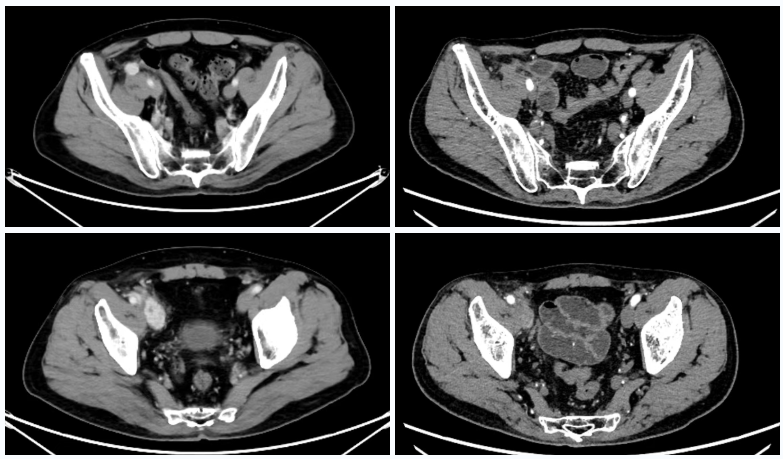

诊断:转移性右肾透明细胞癌(双肺,右侧腰大肌前缘及髂外血管旁淋巴结转移(T1N0M1,Ⅳ期)

△2023年2月患者基线时CT(左)与2024年4月时CT(右)检查所见对比

△2025年8月疗效评估时患者CT检查(右)较基线(左)对比